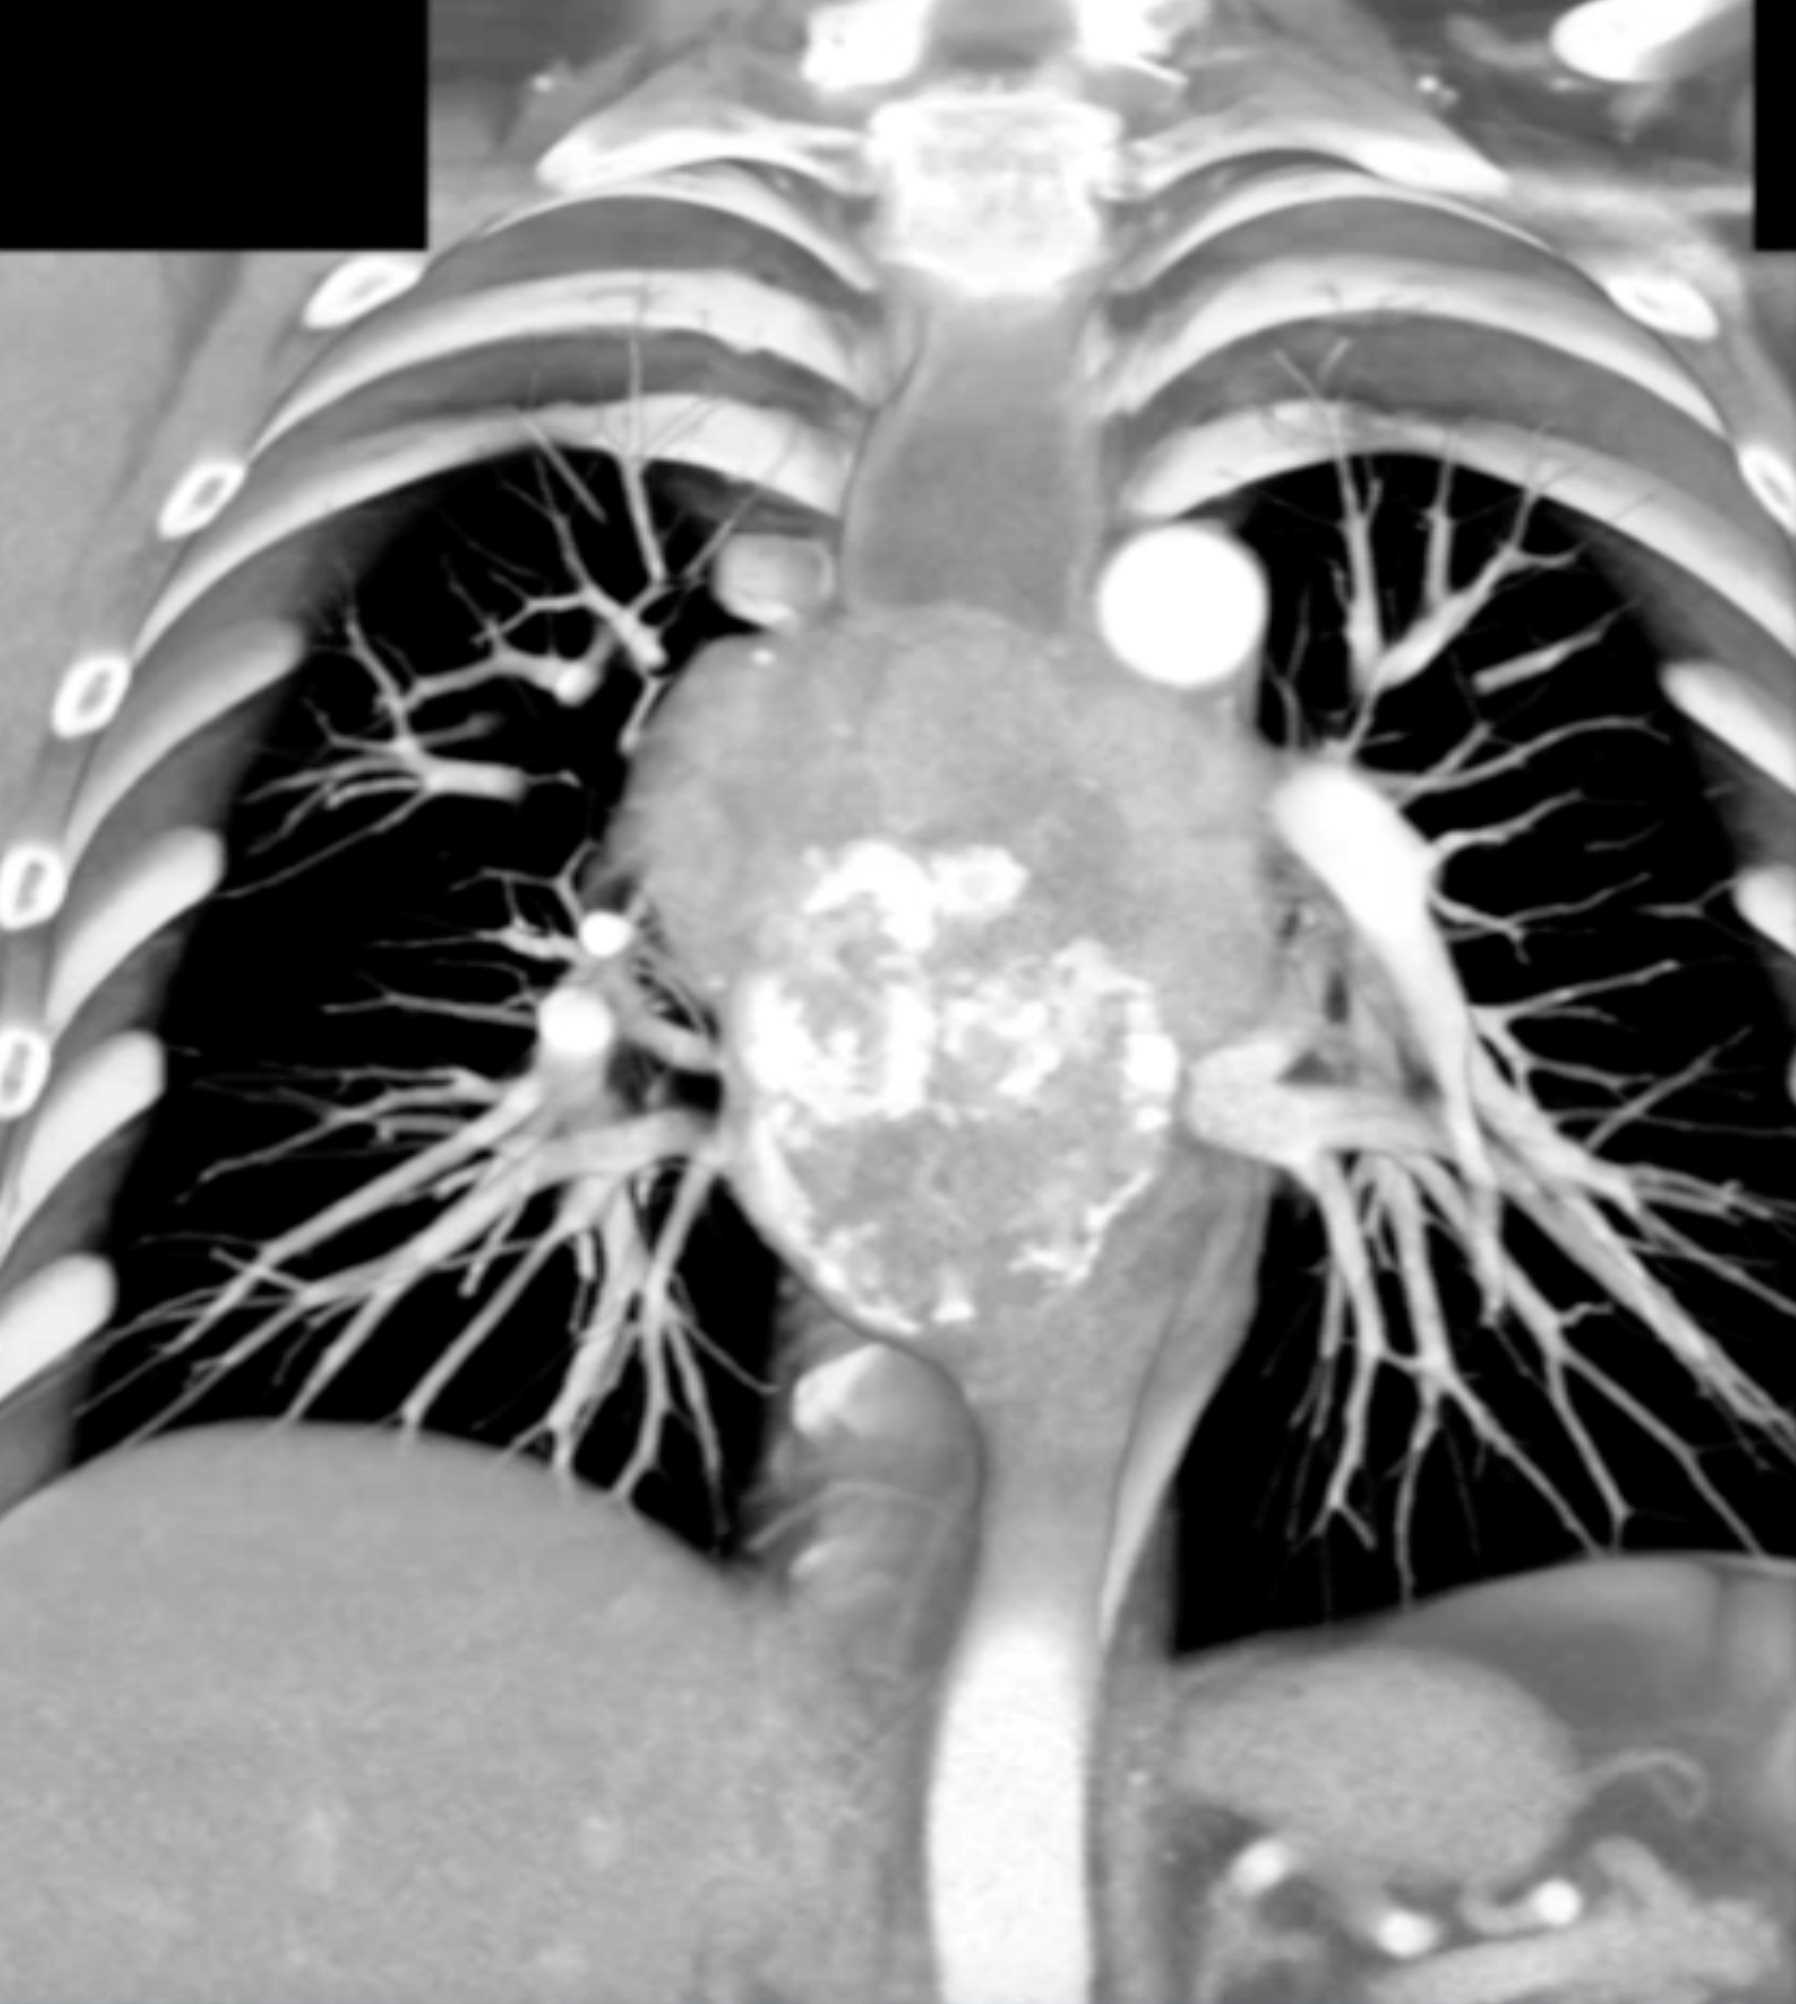

Fibrosing Mediastinitis